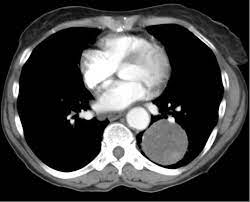

A large hamartoma of the spleen. Multiple hamartomas throughout the body occur in cowden's disease. A description of popcorn calcification—meaning images that look like popcorn on a ct. Endobronchial hamartoma resected by rigid bronchoscope. A mass resembling a tumor that represents anomalous development of tissue natural to a part or organ rather than a true tumor. Most isolated hamartomas are benign but in cowden's disease there is a risk that one or more may undergo malignant change.4. High magnification shows the 3 components of fhi. Report of two cases and comprehensive review of the literature.

A large hamartoma of the spleen. A rare cause of bronchial occlusion. Hamartoma, benign tumourlike growth made up of normal mature cells in abnormal number or distribution. A hamartoma (from greek hamartion bodily defect) is a benign (noncancerous) tumorlike malformation made up of an abnormal mixture of cells and tissues found in areas of the body where growth occurs. A hamartoma is a focal malformation that resembles a neoplasm in the tissue of its origin. This is not a malignant tumor, and it grows hamartomas, while generally benign, can cause problems due to their location. This zone shows sheets of immature cells with bland, ovoid vesicular nuclei. It is considered a developmental error and can occur at a number of sites. A mass resembling a tumor that represents anomalous development of tissue natural to a part or organ rather than a true tumor. Breast hamartomas are responsible for roughly 5 percent of benign breast masses. A large hamartoma of the spleen. Hamartomas can be difficult to distinguish from cancers but do have some characteristics that set them apart. Residents and fellows contest rules | international ophthalmologists contest rules.

Report of two cases and comprehensive review of the literature. Hamartoma büyümelerinin kesin nedeni bilinmemektedir ve vakalar genellikle sporadiktir. A large hamartoma of the spleen. May have recurrent genetic translocations. A hamartoma is a benign, focal malformation that resembles a neoplasm in the tissue of its origin. While traditionally considered developmental malformation, many hamartomas have clonal chromosomal aberrations that are acquired through somatic mutations and on this basis are now considered to be neoplastic. Multiple benign hamartomas are called proteus' syndrome.5the condition reached public attention. A description of popcorn calcification—meaning images that look like popcorn on a ct. Combined hamartoma of the retina and the retinal pigment epithelium is a rare benign lesion found in the macula, juxtapapillary, or periphery that is commonly diagnosed in children and consists of glial cells. Hamartoma, benign tumourlike growth made up of normal mature cells in abnormal number or distribution. The hamartoma is the dark circular object on the left that dominates the image. If #2 does not apply it is a choristoma. Composed of tissue of the region within it is found.